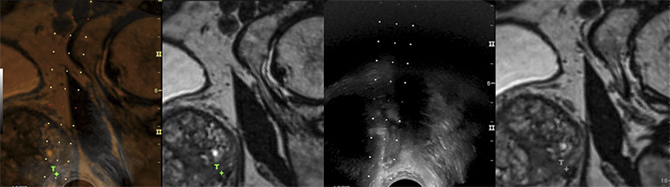

Biopsia Prostatica Orientada Por Fusao De Imagem Rmn Etr Breve Revisao A Proposito De Caso Clinico Acta Urologica Portuguesa

Pdf Biopsia Prostatica Orientada Por Fusao De Imagem Rmn Etr Breve Revisao A Proposito De Caso Clinico

Pdf Biopsia Prostatica Dirigida Por Fusao Cognitiva Apos Ressonancia Magnetica Multiparametrica Comparacao Com A Tecnica Habitual De Biopsia Aleatoria